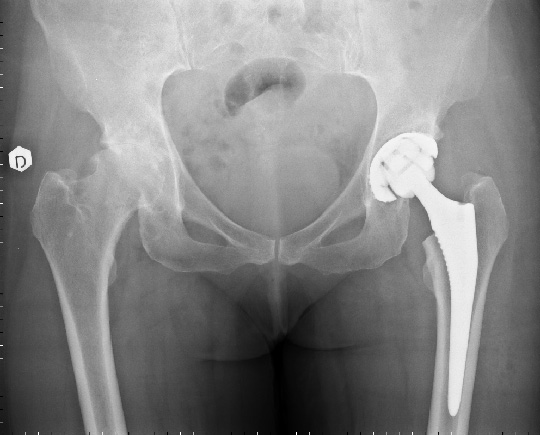

Un esempio e una radiografia di una protesi totale del'anca

Una protesi articolare è composta da uno stelo femorale di solito in titanio, una coppa acetabolare anch'essa in titanio. La testa femorale e l'inlay sono disponibli in metallo, polietilene oppure ceramica.

A seconda della qualità ossea le componenti possono essere cementate o non.